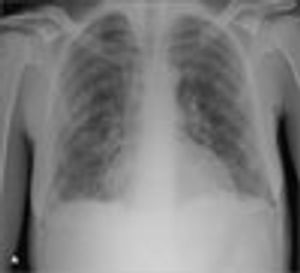

For 3 days, a 45-year-old woman with HIV infection who was noncompliant with her antiretroviral medications had cough, yellowish sputum, fever, and dyspnea. She denied hemoptysis, weight loss, or recent hospitalization. She had a long history of heavy smoking and alcohol and intravenous drug abuse.